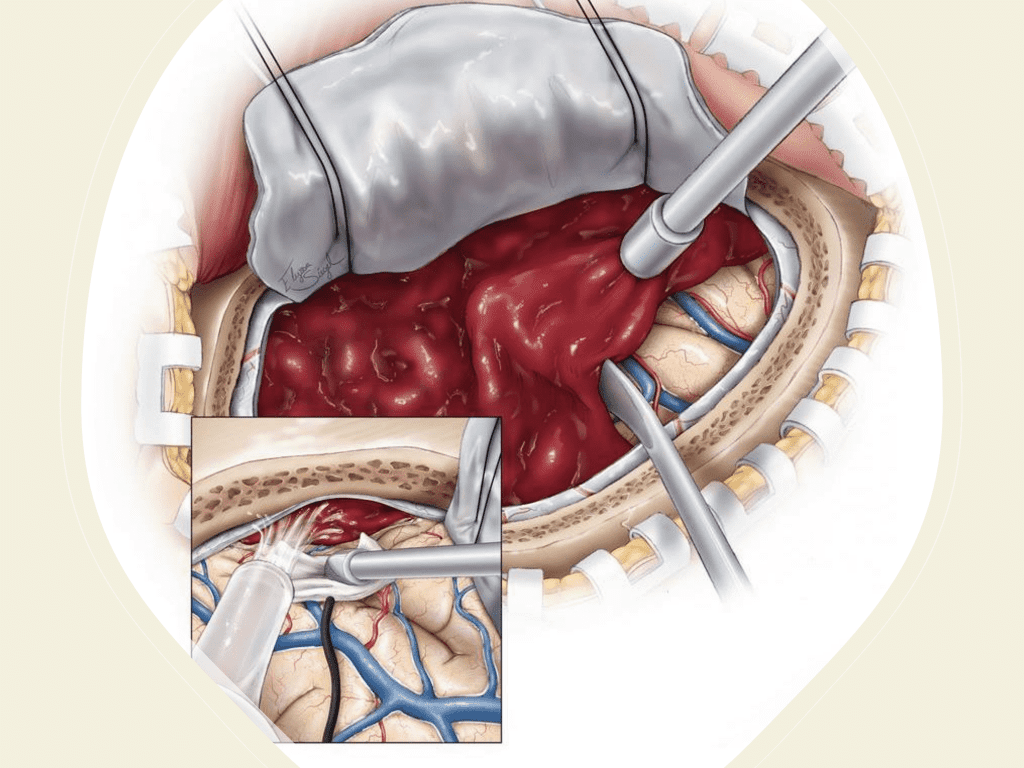

The treatment and management of cSDH remains controversial and has traditionally been treated either conservatively with observation and serial imaging in asymptomatic patients and smaller collections (without midline shift) or more aggressively with surgical evacuation in symptomatic patients or larger collections (with greater than 5 mm of midline shift). There is a variety of surgical options for cSDH treatment including twist-drill craniotomy (5-10 mm incision) with or without a subdural evacuating port system (SEPS), burr hole evacuation (silver dollar or up to 30mm incision) with or without drains, or craniotomy (>30 mm incision). Irrespective of the type of evacuation, cSDH surgical treatment continues to have high recurrence rates ranging from 5% to 37%, thereby subjecting these patients to repeat surgical interventions, hospital admissions, and the associated complications including peri-operative morbidity, diminished neurologic and functional status, and even mortality (5).

Figure 6. Surgical craniotomy for Subdural Hematoma. (https://www.neurosurgicalatlas.com/volumes/emergency-neurosurgery-and-trauma/traumatic-hematoma/acute-subdural-hematoma((c)2022, The Neurosurgical Atlas) (6).

Although conventional surgical methods, such as burr hole irrigation or observation in asymptomatic or minimally symptomatic patients have been the mainstay of treatment, middle meningeal artery (MMA) embolization has emerged as a promising adjunctive or alternative treatment. MMA embolization is a neuroendovascular technique which involves placing a microcatheter into the Middle Meningeal Artery, most commonly on the side of the cSDH (occasionally, bilateral embolization has been recommended for larger or bilateral collection. Embolization of both the anterior (frontal) and posterior (parietal) division is performed using a variety of embolic materials (liquid NBCA, Onyx, coils), although polyvinyl alcohol particles of <250 microns are most commonly used to achieve distal penetration and occlusion of the pre-capillary and capillary beds. The micro-leakage of blood and transudative proteinaceous inflammatory fluid in these inflammatory membranes is creating an imbalance in cycle of resorption and preventing resolution or promoting recurrence or growth of these cSDH collections and associated mass effect and midline shift.